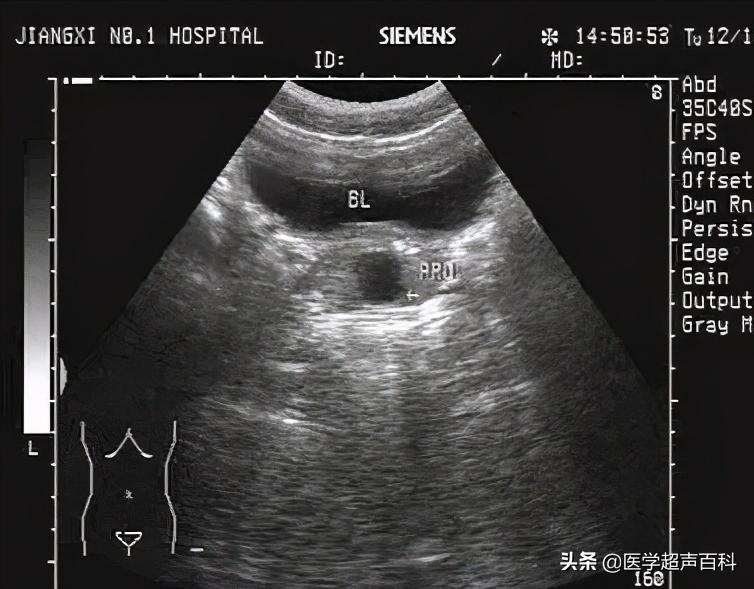

超声表现

前列腺大小无改变或变化不大;包膜清晰、完整,左右对称;前列腺内见无回声区,壁较薄,后方回声增强,大小不等,可位于前列腺内部,也可位于前列腺包膜上,先天性多位于后叶,后天性囊肿可位于前列腺任何部位,前列腺囊肿较大时可突入膀胱内。前列腺囊肿可与前列腺炎、前列腺增生、前列腺结石同时存在。经直肠前列腺超声可提高诊断率。